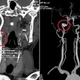

Theo Bệnh viện Nhi Thanh Hóa, rò xoang lê là bệnh lý bẩm sinh do còn tồn tại túi mang III, IV từ thời kỳ bào thai. Ở Việt Nam rò xoang lê chiếm tỷ lệ rất cao 51.92 – 73.68% trong các bệnh lý nang và rò mang bẩm sinh vùng cổ bên.

Bệnh này thường khởi phát chủ yếu ở trẻ em với biểu hiện u nang vùng cổ bên, áp xe vùng cổ tái diễn nhiều lần, sưng tấy, áp xe vùng tuyến giáp nên dễ nhầm với áp xe tuyến giáp, viêm tuyến giáp cấp mủ, áp xe hạch.

Đây là một bệnh lý phức tạp, liên quan giải phẫu với những cấu trúc quan trọng vùng đầu cổ, biểu hiện đa dạng, có thể xơ dính do quá trình viêm nhiễm tái đi tái lại.